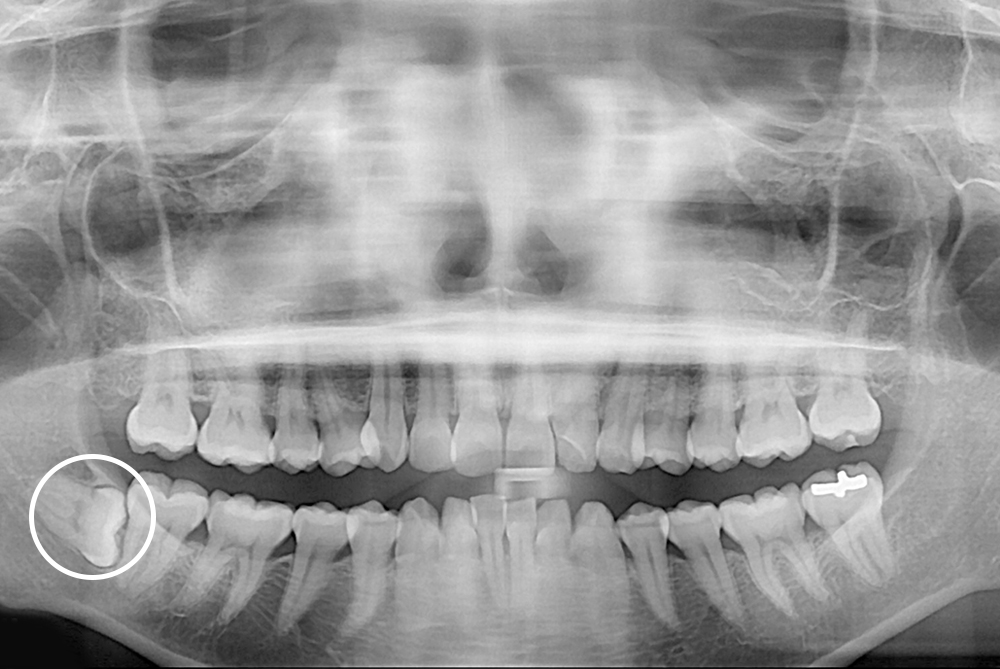

[사랑니] 매복 사랑니 발치

치료후 : 2019-04-03

세종치과는 구강악안면외과학 박사이신 원장님이 발치하는 치과입니다.